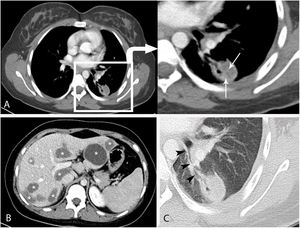

A 22-year-old female presented with complaint chest pain and abdominal pain. Contrast-enhanced thoracoabdominal computed tomography (CT) showed some well circumscribed heterogeneous nodules in the lung. And multiple cystic lesions were also seen in the liver (Fig. 1B) An echinococcus hemagglutination test was positive and hydatid cyst was considered. The patient was started oral albendazole treatment and was planned PAIR (puncture-aspiration-injection-reaspiration) treatment for liver and surgical treatment for lung after albendazole treatment. But two days later, before surgical treatment, she was admitted to the emergency department with a complaint of yellowish hemoptysis containing membranes. When the patient applied to the emergency service, her hemoptysis had already stopped spontaneously. The patient described a hemoptysis of about 60ml. Therefore, the cause of hemoptysis was investigated. There was no trauma history. Contrast-enhanced chest CT demonstrated a nodule with a heterogeneous density and an air bubble inside in the left lower lobe which was communication with a bronchial branch (Fig. 1A,C). The patient was surgically treated with cystectomy and 10mg/kg/day albendazole treatment was prescribed. Finally, pulmonary hydatid cyst was confirmed by surgery. The patient was diagnosed with spontaneous endobronchial rupture of pulmonary hydatid cyst.

Contrast-enhanced axial computed tomography (A) showed a heterogeneous nodule in the lower lobe of the left lung with air bubbles and internal germinative membranes (arrows). There was an increase in cyst density due to germinative membranes. Computed tomography (B) showed multiple well circumscribed hypodens hydatid cystic lesions in the liver (Asterisks). Computed tomography, lung window(C) showed the communication between the cyst and a bronchus (arrowheads).

Hydatid disease is a rare disease in human which occurs by the larvae of the Echinococcus. The disease is transmitted by contamination of food and water. Hydatid disease commonly involves the liver and lungs.1 The clinical presentation of the disease is non-specific. The diagnosis is confirmed by radiology supplemented with serology. The detection of germinative membrane on CT is diagnostic in the diagnosis of hydatid cyst.2 In addition, the presence of calcification may help in diagnosis.2 The presence of air bubbles is an important finding for the diagnosis of cyst rupture.2 The treatment of pulmonary hydatid cyst is either medical and/or surgical.3